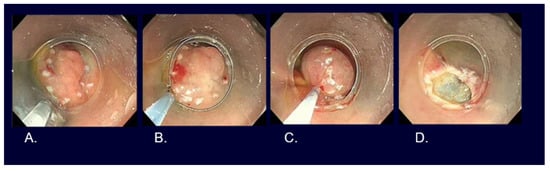

5. Types of Endoscopic Resection for Early Gastric Cancer